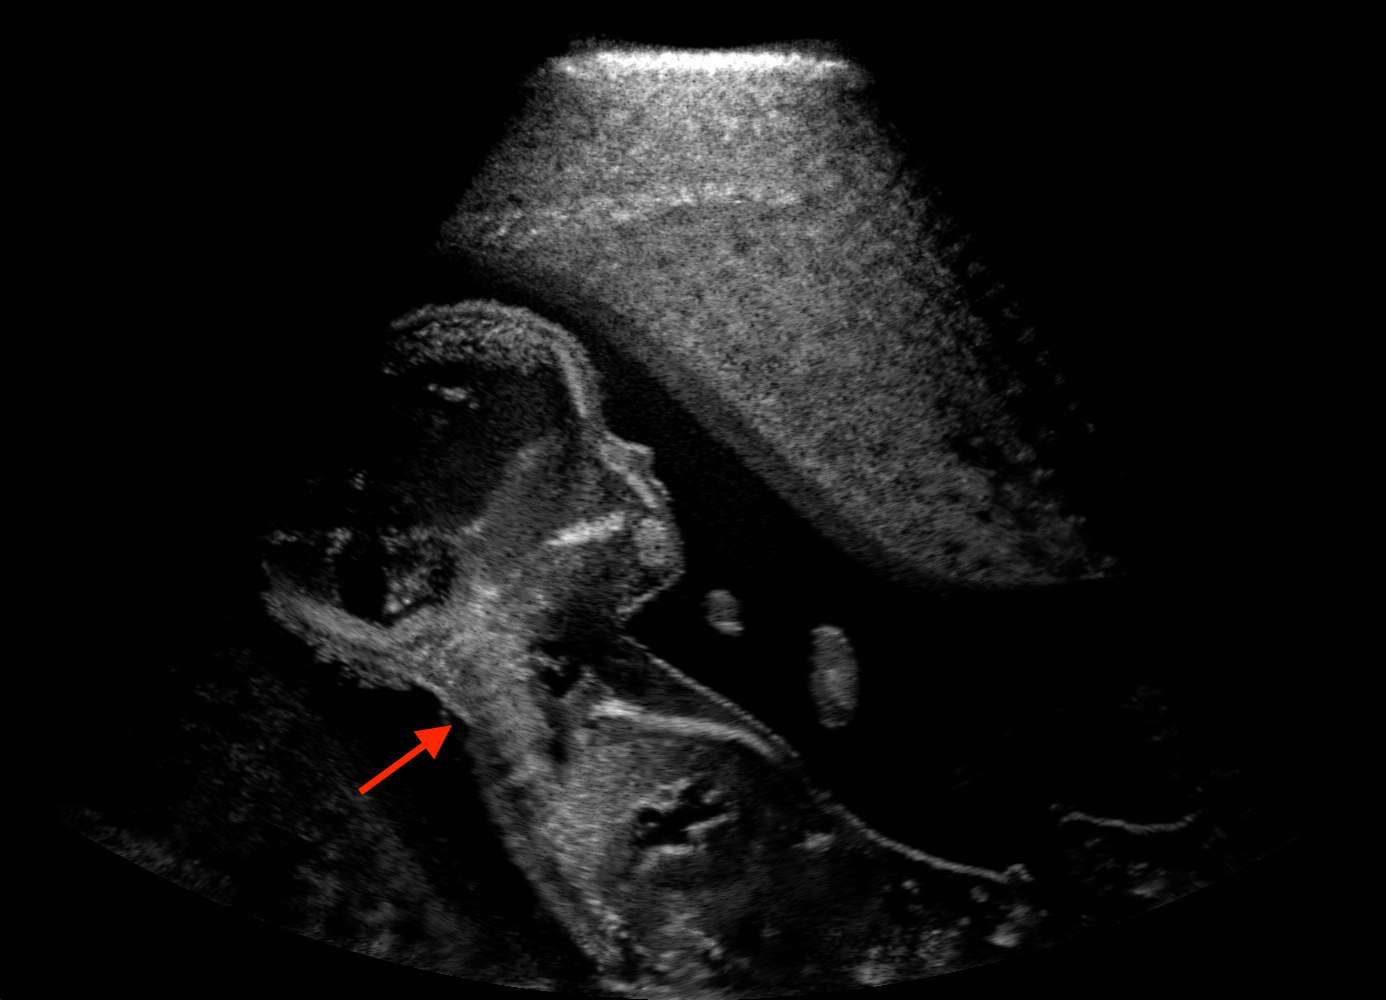

For the interpretation of the local errors, sample spatial p error maps are depicted in Fig. 3 for LSA2H, NSA2H, and SA2H for the middle two examples shown in Fig. 2. Both images generated by NSA2H have a lot of missing structures and accordingly have high error almost all over the map. Artificial skull enhancement with LSA2H is seem to evoke large p error, as shown in the corresponding error map, whereas the bright spots in the error map of SA2H reflect some hallucinated shadows and structure in the brain. All of above mentioned regions of interest are marked by red arrows. In the bottom example, SA2H fails to generate faithful content at the bottom region marked by red circles, which is well indicated by the error map as well.